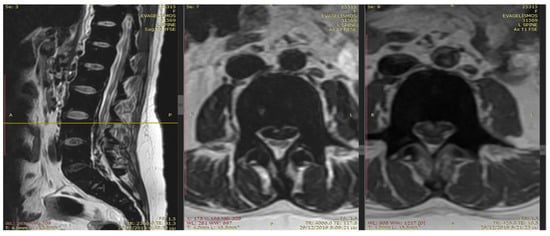

An emergency MRI was conducted on the patient, and the findings can be succinctly summarized as follows. In the T2 sequence, a low signal is observed in the anterior epidural space, accompanied by an uneven signal in the T1 sequence. These observations indicate compressive effects on the dura at the level of L2, extending towards the posterior segments of the spinal canal up to the final segment. Furthermore, a portion of this compression appears to extend along the midline fissures on the right side, particularly at the levels of L5–S1 and S1–S2, causing mild compressive effects on the nerve roots. In the GRE sequence, a low signal is noted in a segment of the aforementioned distribution, raising strong suspicion of hemosiderin deposition (Figure 1 and Figure 2). In the fat-suppressed T2 sequence, there is a diffuse increase in signal, signifying edema, in the soft tissues at the level of the midline fissures in the posterior elements and the soft tissues between the ligamentum flavum and the dura at the intervertebral foramina level. Additionally, edema is observed in the epidural space.

Figure 2.

In the T2 sequence, there is a low signal in the anterior epidural space, along with an inhomogeneous signal in the T1 sequence. These findings suggest compressive effects on the dura at the level of L2, extending to the posterior parts of the spinal canal until the final segment. Additionally, a segment of this compression seems to extend along the course of the midline fissures on the right side, specifically at the levels of L5-S1 and S1-S2, causing mild compressive effects on the nerve roots.